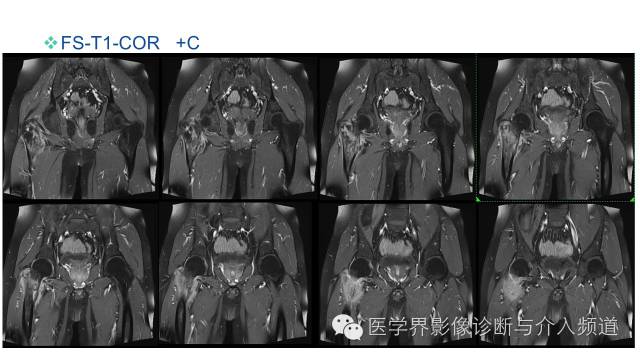

MR平扫及增强示:

右侧股骨上段见不规则形长T1短等T2异常信号,直径约1.5cm,邻近骨皮质破坏,其内骨髓可见斑片状长T1等长T2混杂信号,边界不清,股前方可见软组织肿块,呈长T1等长T2混杂信号,DWI呈明显高信号;注入GD-DTPA后,股骨内病灶呈轻度强化,周围软组织呈明显不均质强化。左侧髋关节诸组成骨对位关系可,未见明显骨质破坏征象,双侧髋关节可见少量斑片状长T2液体信号影。